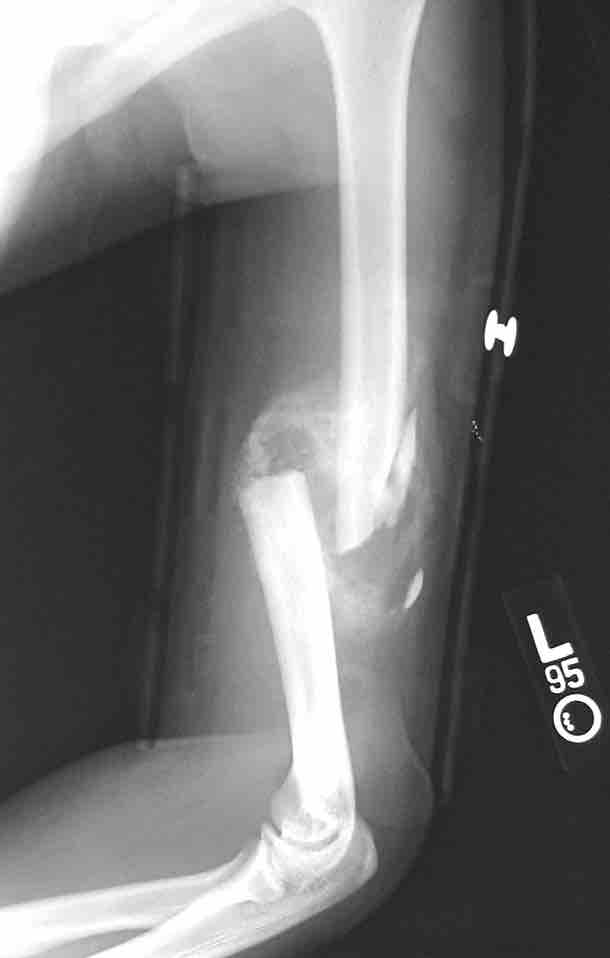

This figure depicts a communitive midshaft humeral fracture with callus formation.